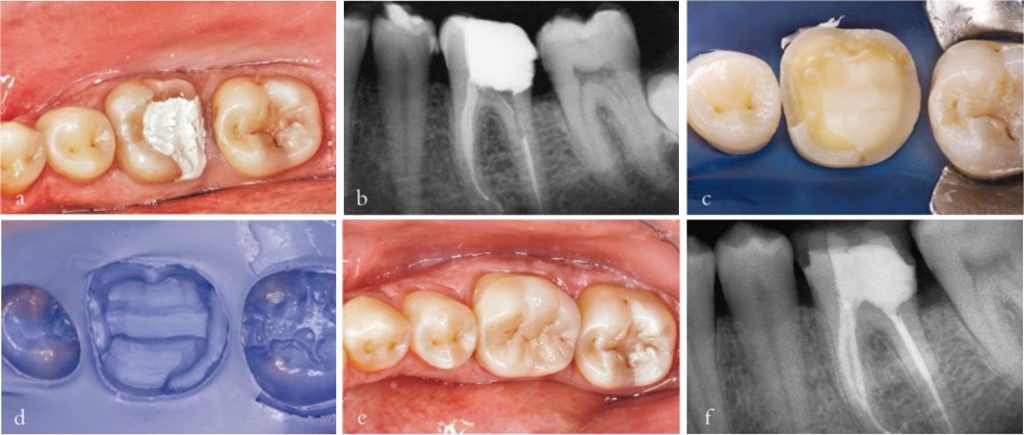

Phục hồi amalgam với che phủ múi răng ít nhất 2 mm có chi phí thấp và đáng tin cậy, đặc biệt ở răng cối lớn hàm dưới (Hình 3-8), nhưng mối quan tâm về thẩm mỹ ngày càng tăng đã hạn chế việc sử dụng ở những răng quan trọng về thẩm mỹ, đặc biệt là răng cối nhỏ hàm trên.

Ở răng hàm trên, bắt buộc phải phủ các múi chức năng, đặc biệt là “múi trong”, còn việc phủ các múi ngoài có thể được bỏ qua nếu chúng không tiếp xúc trong các vận động bên.

Ở răng hàm dưới, tất cả các múi cần được phủ. Nếu buồng tủy sâu dưới 4 mm, cần đặt chốt kim loại để đảm bảo cố định cùi giả amalgam; thông thường kéo dài 3 mm amalgam vào ống tủy là đủ.

Mão sứ – kim loại là giải pháp phục hồi được sử dụng rộng rãi nhất, cả cho mão đơn phía sau lẫn các răng làm trụ cầu (Hình 3-11).